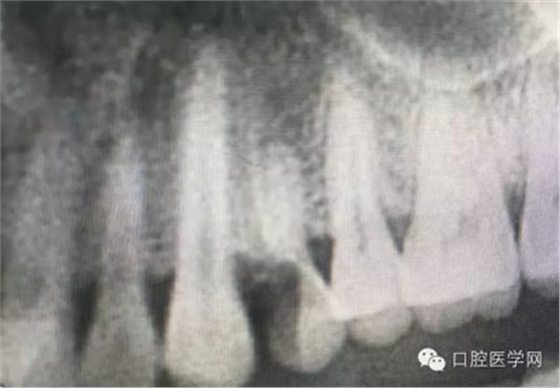

根管再治療是我們比較頭疼的,尤其是那些冠修復(fù)過(guò)的,我們有很多的麻煩需要去溝通,比如可能導(dǎo)致的側(cè)穿、可能沒有看到的腐質(zhì)、可能導(dǎo)致的崩瓷,或者是后期可能出現(xiàn)冠折......這些需要我們和患者好好的溝通。全瓷冠還好些,金屬冠根測(cè)的時(shí)候很是麻煩,總之我們做修復(fù)的時(shí)候不要單純的追求速度,追求效益,適當(dāng)?shù)淖⒁庀挛覀兊幕A(chǔ)治療和設(shè)計(jì)。

這是一例外院樹脂修復(fù)后十個(gè)月出現(xiàn)牙髓炎癥狀的患者。遇到這樣子的患者大家會(huì)怎么做,證明選擇,還有就是可做可不做治療的如何去平衡。